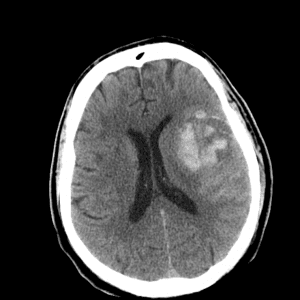

Case #3